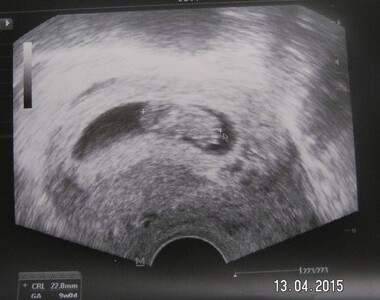

Příští týden mě čeká kontrolní ultrazvuk a tak se těším, že už si odnesu i fotku miminka. Chtěla bych s paní doktorkou probrat ty nevolnosti a braní čípků a také to krvácení, které ťuk ťuk ustalo.